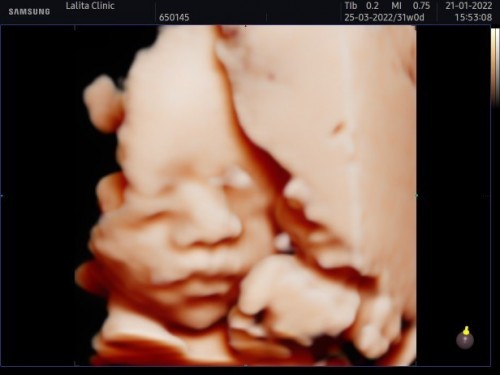

หนูชื่อน้องอลินค่ะ อัลตราซาวด์4มิติตอน 30w นน.1600 วันนี้ไปหาคุณหมอ 34w นน. หนุขึ้นมา2200แล้วนะคะ แม่ดีใจสุดๆ ทีคลอด 23/3/65🥰🥰🥰